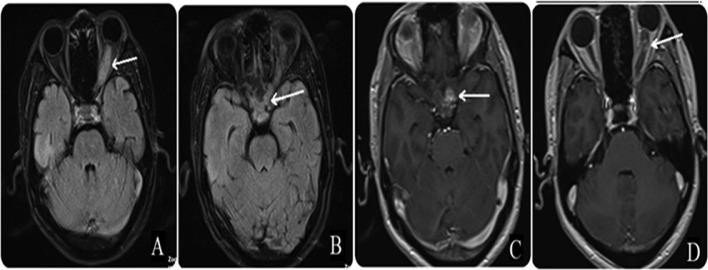

Glioma has been previously known as the most common adult brain tumor. Glioma of the optic pathway is predominated by low-grade neoplasms. High-grade glioma in adults is extremely rare. In this study, we present the case of a 46-year-old male patient who developed glioblastoma of the optic chiasm extending along the optic tract. This study aims to discuss several common differential diagnoses of nontumor diffuse lesions in the optic pathway and their clinical symptoms and magnetic resonance imaging findings, which could help navigate management.

胶质瘤此前一直被认为是最常见的成人脑肿瘤。视神经通路胶质瘤以低级别肿瘤为主。成人高级别胶质瘤极为罕见。在本研究中,我们报告了一例46岁男性患者,其发生了沿视束延伸的视交叉胶质母细胞瘤。本研究旨在探讨视神经通路非肿瘤性弥漫性病变的几种常见鉴别诊断及其临床症状和磁共振成像表现,这有助于指导治疗。